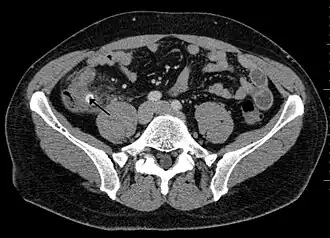

![]() Fecaloma rectal en un paciente hospitalizado. Presenta, además, una neovejiga y aterosclerosis. TC abdominal. | ||